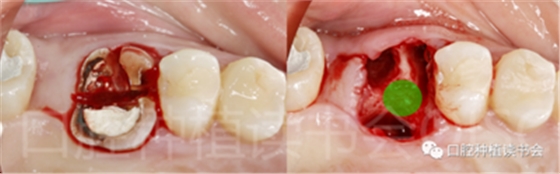

5.3.2 逐級預備種植窩洞后,側(cè)切鉆分根,微創(chuàng)拔除殘根,探查頰、舌側(cè)骨板完整,仔細搔刮拔牙窩,生理鹽水沖洗(圖15)。

圖15 微創(chuàng)拔牙后確認種植窩洞位于牙槽間隔內(nèi)。

5.3.3 根據(jù)拔牙窩內(nèi)的牙槽間隔高度,植入康盛CANSUN柱形親水種植體(4.3*8mm),確保種植體肩臺與牙槽間隔平齊,種植體的所有表面均被自體骨包繞(圖16),植入扭矩為25N.cm。

圖16 盡量讓種植體表面被牙槽間隔的自體骨包繞。

5.3.4 旋入覆蓋螺絲,在種植體與四周骨壁的間隙內(nèi)植入 Bio-Oss Collagen,植骨材料用生理鹽水濕潤后,用15#刀片分割為小塊分別植入,并用充填器壓實(圖17)。

圖17 后牙即刻種植植骨推薦使用骨膠原材料,有利于軟組織愈合。